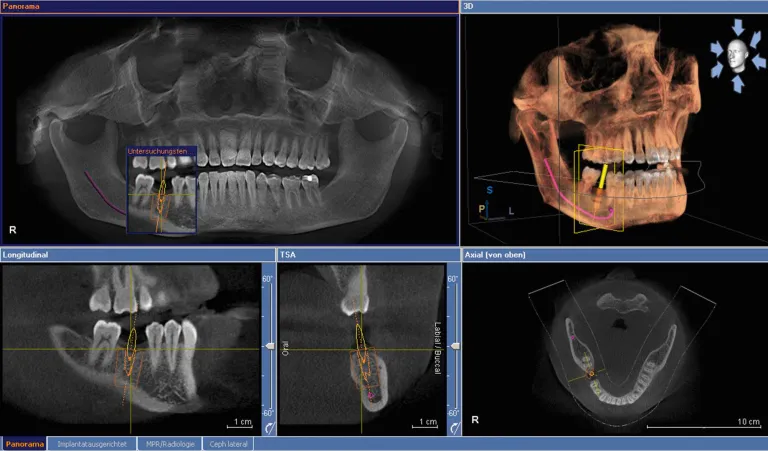

Cone Beam CT Scanning & Computer-Guided Implant Planning

Dental CT 3D imaging is becoming the standard of care in dental implantology. This 3D radiographic image provides a detailed mapping of the anatomy so that implants can be placed more quickly, more accurately, and with a much higher level of comfort and safety. Quality, predictability, and reliability of treatment is our priority at IMPrESS Perio Implant Center. In implant dentistry, we are able to provide all that with the use of the CT scan and planning software in our office.